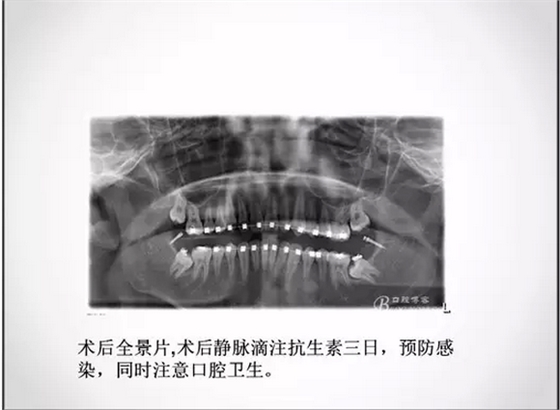

埋伏牙正畸治療中的外科開窗術(shù)